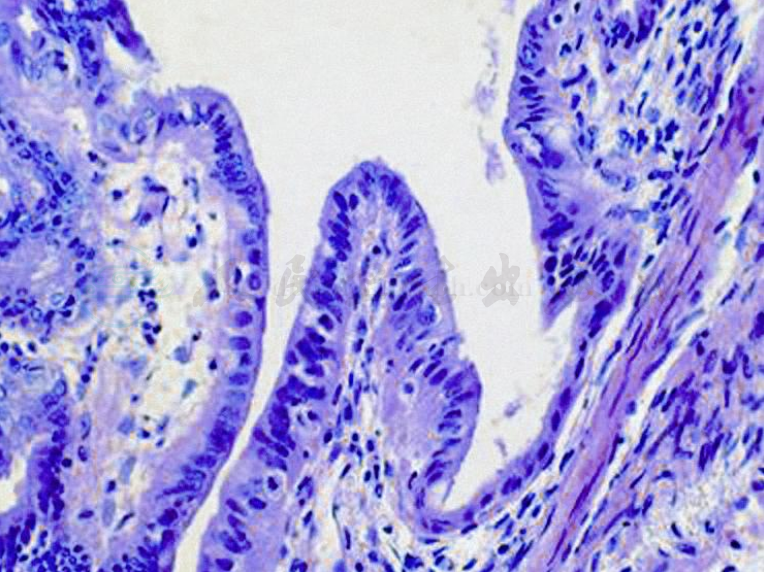

良性瘤囊腔由单层立方或矮柱状上皮衬覆,具有纤毛,与输卵管上皮相似,虽有乳头状结构形成,但一般乳头较宽,细胞形态较一致,无异型性(图1)。交界瘤上皮细胞层次增加,达2~3层,乳头增多,细胞异型,无破坏性间质浸润;新近的研究证明间质浸润灶不超过10mm2的交界性浆液性乳头状囊腺瘤的预后和无间质浸润的交界性浆液性乳头状囊腺瘤的预后相似,称为具有微小浸润的交界性浆液性乳头状囊腺瘤。浸润的细胞和交界性浆液性乳头状囊腺瘤的细胞形态相似,呈单细胞,实体状,乳头状或筛状,单灶性或多小灶性分布。浆液性囊腺癌除细胞层次增加超过三层外,最主要的特征是伴有明显的癌细胞破坏性间质浸润。肿瘤细胞呈现癌细胞特点,细胞异型性明显,核分裂多见,乳头分支多而复杂,呈树枝状分布,或呈未分化的特点。常可见沙砾体(psammoma bodies)。

图1 浆液性乳头状囊腺瘤

肿瘤呈乳头状生长,表面被覆单层立方上皮形态一致,无异型性

特征是有乳头状生长,可为单房或多房,多房者表面成结节状或分叶状。切面呈单房或多房,囊腔由纤维组织分割而成,内壁可见到乳头生长,乳头分支较粗,乳头状突起之间或其内常可见小的钙化体,即所谓的砂粒体,乳头中心的间质为纤维结缔组织,乳头表面大部分为输卵管型上皮,细胞均匀一致,无或少细胞分裂象。

镜检:肿瘤由复杂的乳头状结构组成,伴纤维血管轴心,其形态类似正常黏膜皱襞,但乳头的分支与数量超出正常输卵管黏膜,似腺瘤样改变。乳头表面被覆单层输卵管型上皮,无明显细胞异型与核分裂。